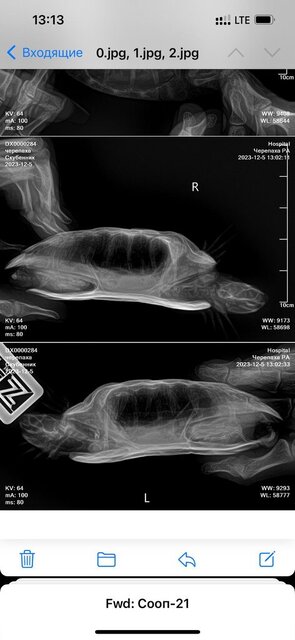

Консультанты moth Ваше имя: Мария Локация: Москва Опубликовано: 2 декабря 2023 Консультанты Опубликовано: 2 декабря 2023 @Инна Марченко активность выше тоже не стала? Вы рентген ей сможете сделать?

Инна Марченко Ваше имя: Инна Локация: Россия, г.Находка Опубликовано: 3 декабря 2023 Автор Опубликовано: 3 декабря 2023 Да, хорошо, записалась в клинику на рентген, правда прием только через 2 дня Пока что продолжаю лечение только каплями?

Консультанты moth Ваше имя: Мария Локация: Москва Опубликовано: 3 декабря 2023 Консультанты Опубликовано: 3 декабря 2023 @Инна Марченко пока да, только капли проекции желательно сделать все три, но хотя бы две - под номерами 1 и 3, чтобы было видно и лёгкие и желудок

Инна Марченко Ваше имя: Инна Локация: Россия, г.Находка Опубликовано: 5 декабря 2023 Автор Опубликовано: 5 декабря 2023 Здравствуйте, вот сделали рентген

Консультанты moth Ваше имя: Мария Локация: Москва Опубликовано: 5 декабря 2023 Консультанты Опубликовано: 5 декабря 2023 @Инна Марченко я отправила снимки нашему врачу, напишу как она ответит сейчас что-то в поведении изменилось в лучшую/худшую сторону?

Инна Марченко Ваше имя: Инна Локация: Россия, г.Находка Опубликовано: 5 декабря 2023 Автор Опубликовано: 5 декабря 2023 Все так же, глазки открываются немного, но не до конца и снова закрываются, уже 9 дней прокапала, кушать все так же отказывается